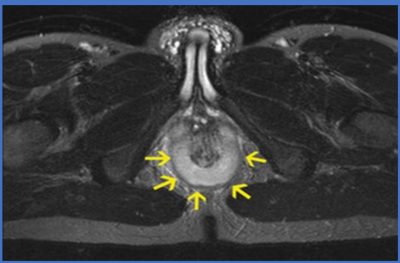

Atnalı fistül değerlendirmesinde MR görüntüleme (MR ) altın standarttır.

- MR

- Tüm tünellerin uzunluğu

• Yan dalların varlığı

• Sfinkter kaslarının ne kadar etkilendiği

• Atnalı yapının hangi düzeyde olduğu

MR, cerrahın operasyon planını en doğru şekilde yapmasını sağlar ve nüks oranını belirgin biçimde azaltır.